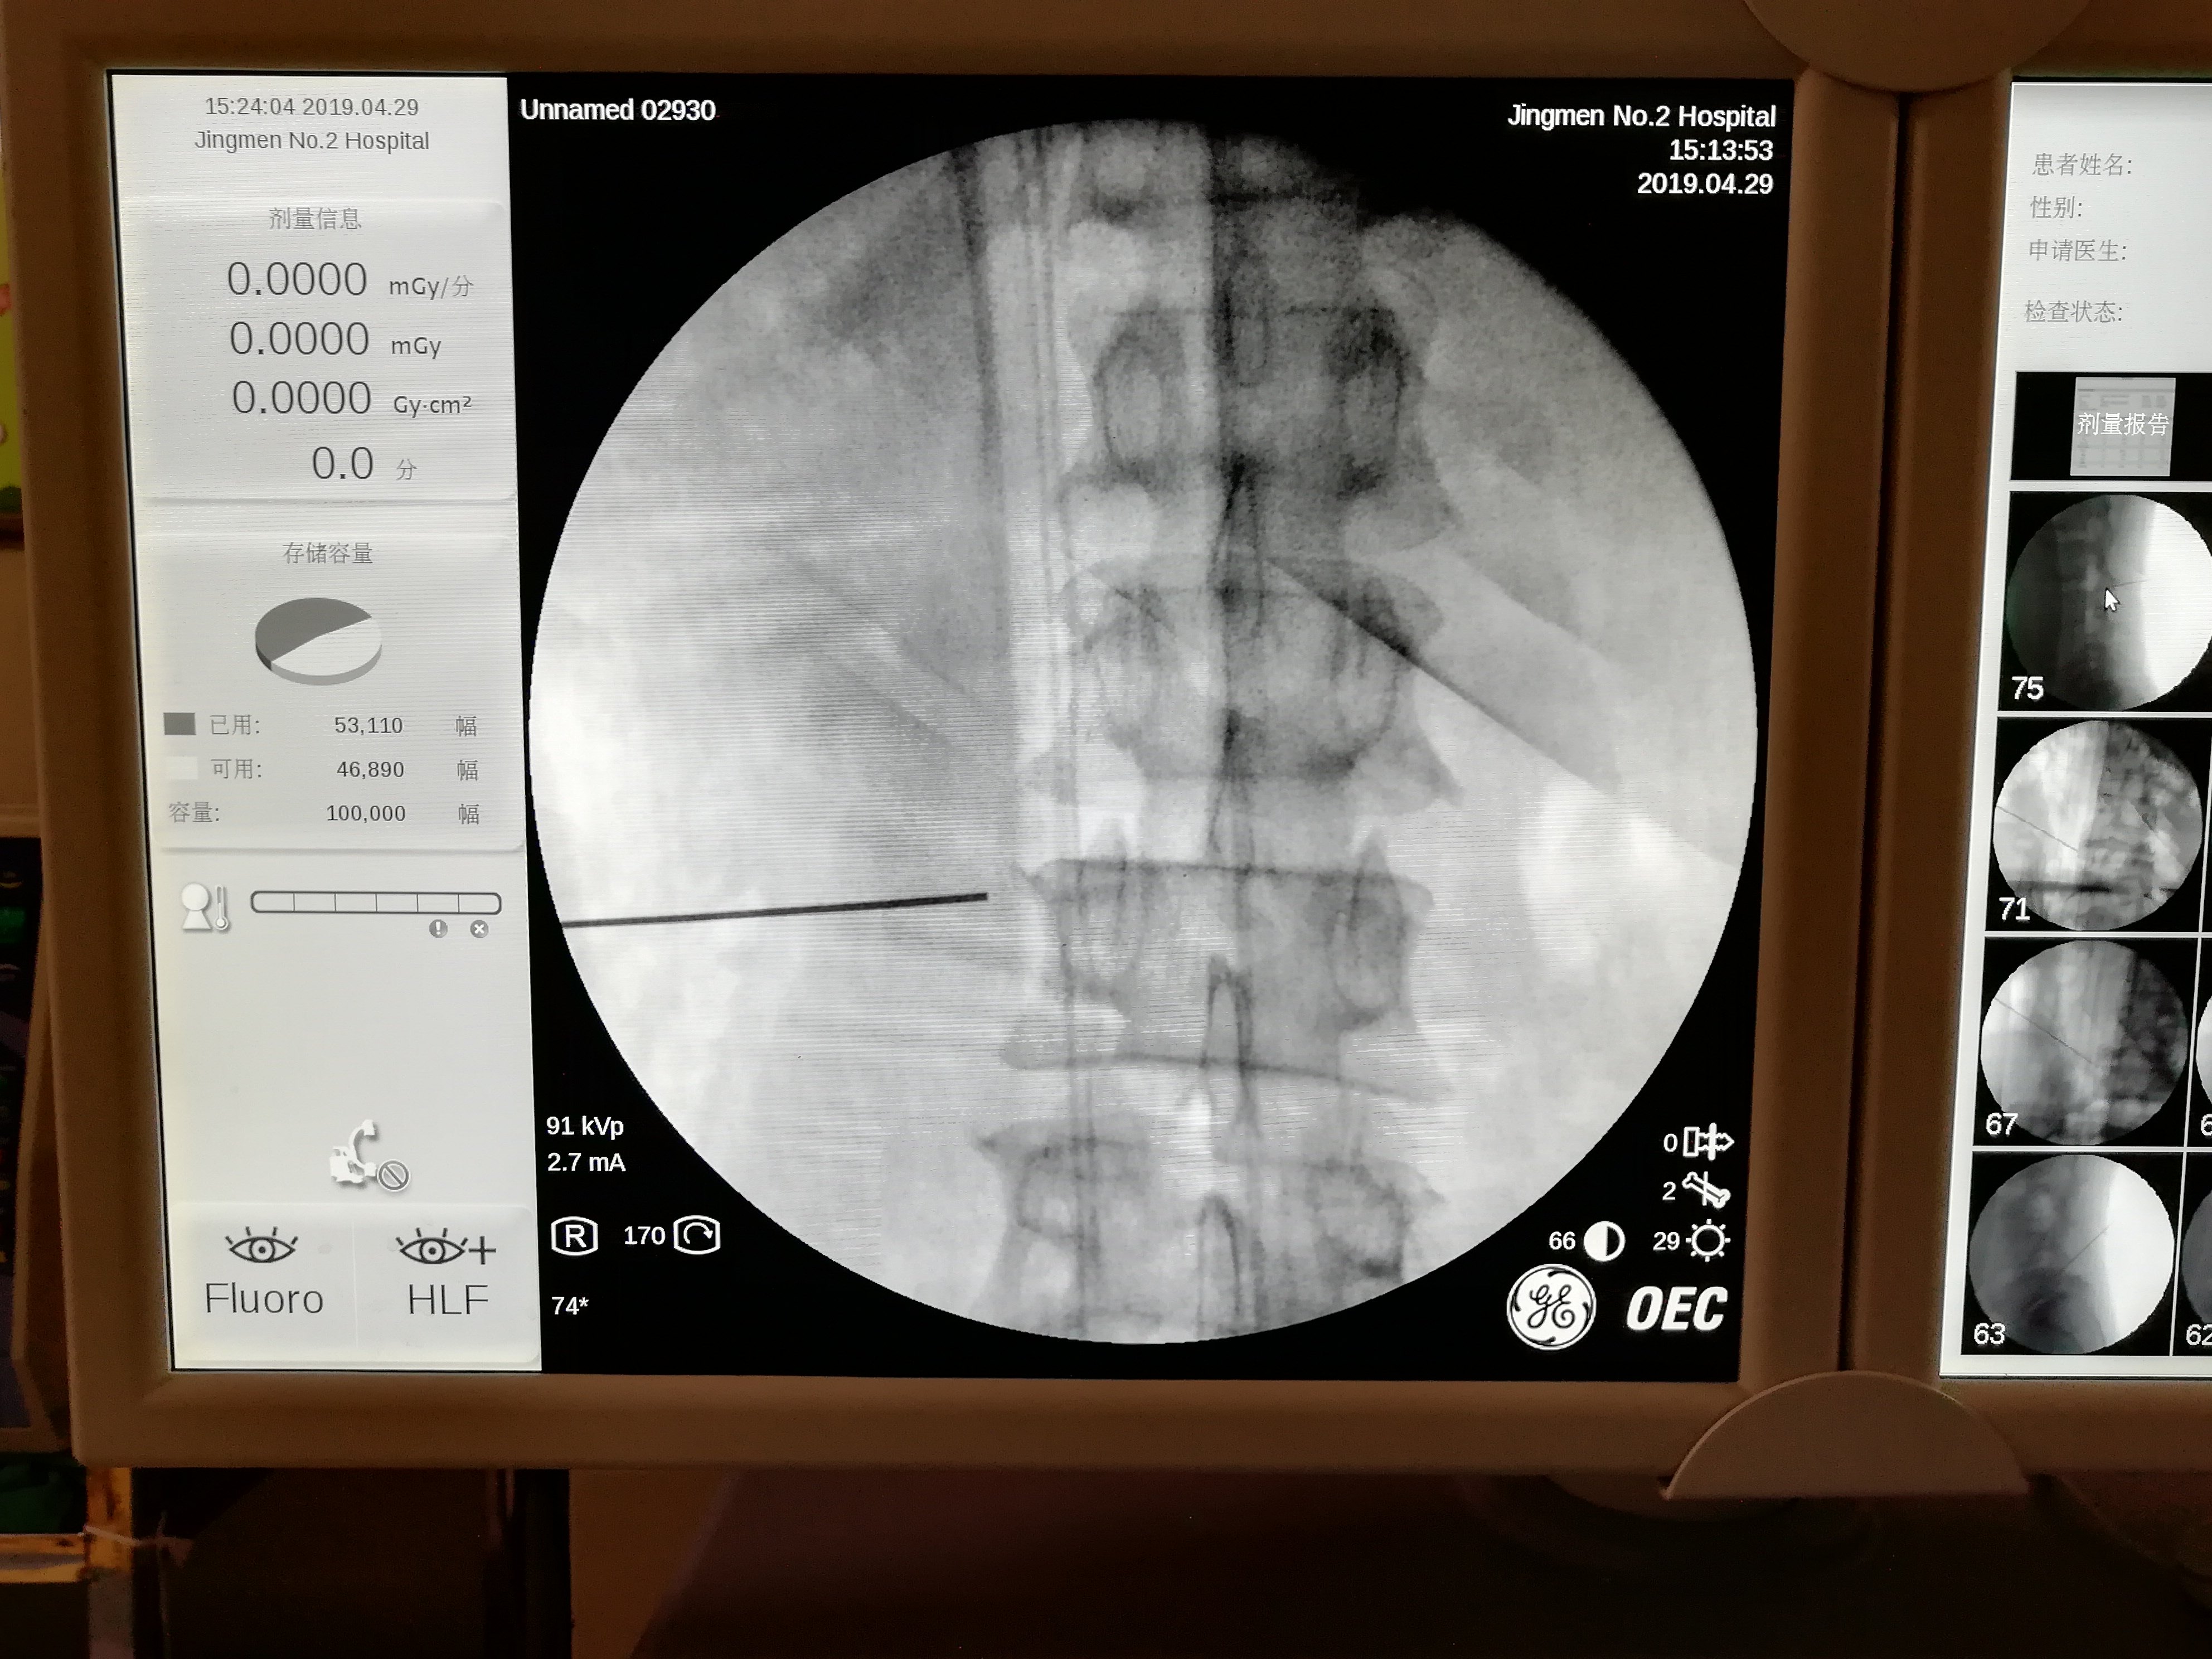

超声频道 | 超声引导下腰交感神经阻滞技术